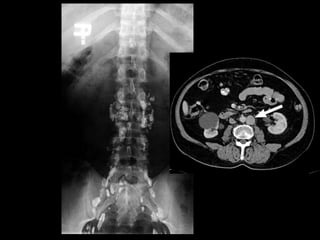

Abdomen

Lymphatic Drainage of

Terminal lymph node

Aortic lymph node

2 types

Pre-aortic

Coeliac nodes

Superior mesenteric

Inferior mesenteric

Para-aortic

Lumbar

Lateral aortic

Lymphatic Drainage of Abdomen